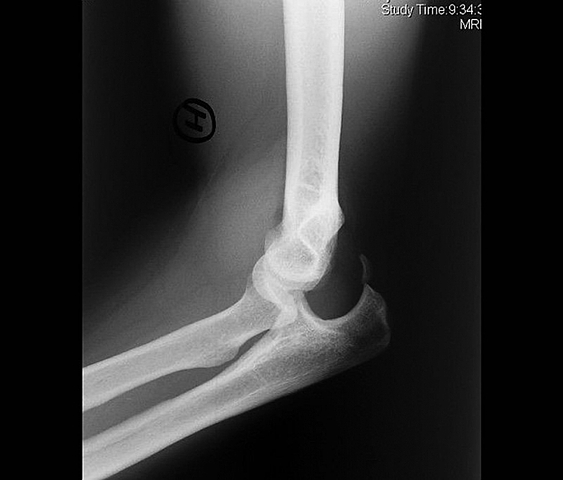

THE ELBOW PRONATION

I took my elbow out three times in two of them I put it without knowing it in the other I had to go to the doctor since there my parents were afraid that in one of those I would break my arm or elbow or something else that could be irreversible